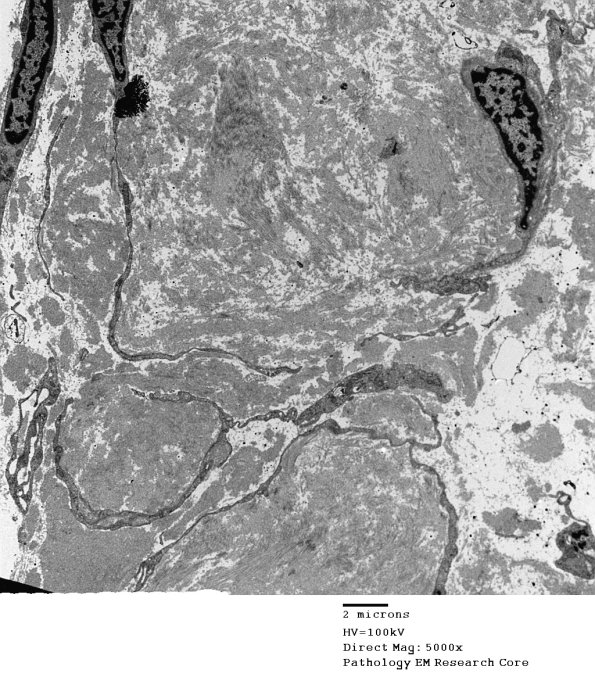

Higher magnification of the RB shows scattered fibroblast-like-cells and their thin processes.